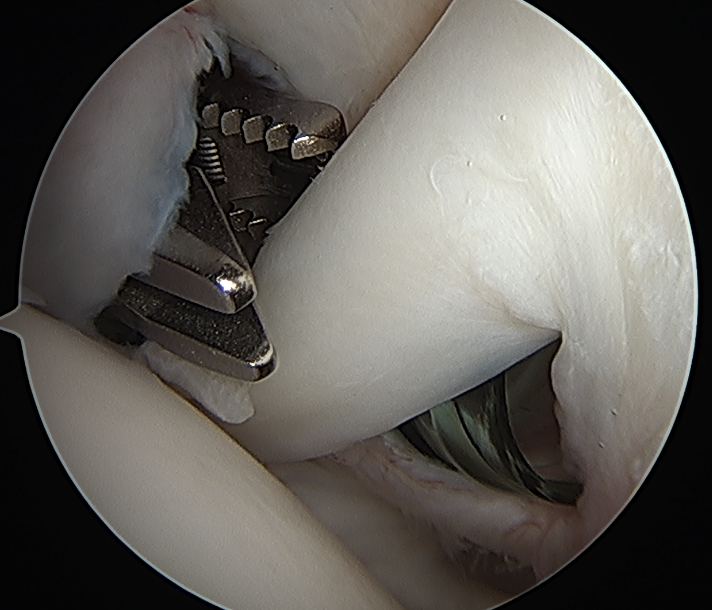

Portal just anterior to supraspinatus tendon

Tag biceps and release